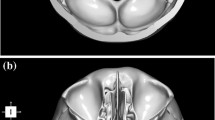

Advanced Normalization Tools software was used to construct a synthetic CT template from 6 subjects, and skull base structures were manually segmented to create a reference atlas. Landmark registration followed by Elastix deformable registration was applied to the template to register it to each of the 30 trusted reference image sets. Dice coefficient, average Hausdorff distance, and clinical usability scoring were used to compare the atlas segmentations to those of the trusted reference image sets.

Currently available open-source algorithms, such as the Elastix deformable algorithm, can be used for automated atlas-based segmentation of skull base structures with acceptable clinical accuracy and minimal corrections with the use of the proposed atlas. The first publicly available CT template and anterior skull base segmentation atlas being released (available at this link: http://hdl.handle.net/1773/46259) with this paper will allow for general use of automated atlas-based segmentation of the skull base.